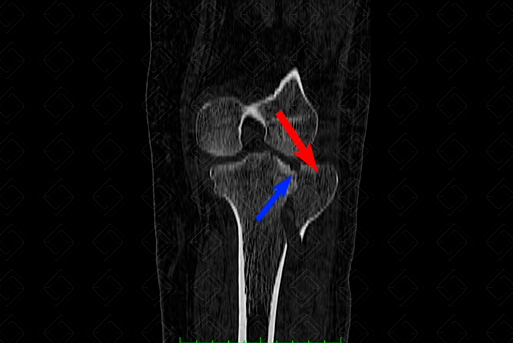

Texto alternativo para a imagem Figura 1. Créditos: Dra. Elazir Mota - Rio de Janeiro/RJ

Descrição da f igura 1: Tomografia computadorizada do joelho esquerdo, janela óssea (esquerda) e de partes moles (direita) evidenciando fratura do platô tibial lateral, com evidente cisalhamento (seta vermelha) e depressão (seta azul), compatível com tipo II , pela classificação de Schatzker. Observe, na janela de partes, o moderado derrame articular na bursa suprapatelar (seta amarela). [cms-watermark]